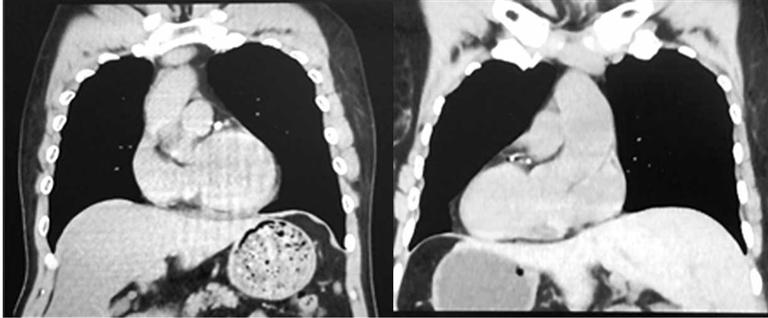

正常人(左)与“镜面人”CT影像对比

泉州市第一医院城东院区胃肠外科主任陈锦萍说:“正常来说,人的心脏在左侧,肝脏在右侧。但该患者从腹部到胸部,所有的脏器全部长反了,也就是所谓的‘镜面人’,即心脏、肝脏、脾脏、胆等器官的位置与正常人相反。在临床中,这种情况的发生率仅百万分之一。”